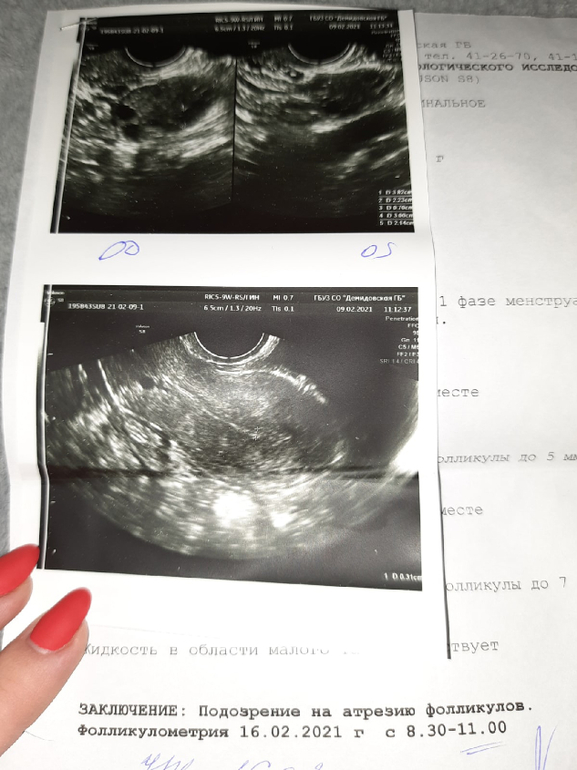

Ждем дня Х (Признаки беременности / Тесты)Всем привет. Вчера писала пост https://www.babyblog.ru/community/post/conception/3540141 я была уверена что реагент, тем более остальные тесты были только с еле заметными полосками. Сегодня с утра сделала эви из голубой пачки , он положительный. Но я не понимаю как такое может быть? По узи (прикрепляю) О не было .Делала еще тесты на О они все положительные ,как в саму О. Может ли тест на Б среагировать на О? Просто вчера ещё и яичник стрелял сильно.

Верить узи, если доктор не проверен, тоже такое себе дело😊 я была на фолликулометрии у врача, он сказал, что у меня воспаление какое то, яичник увеличен, надо лечиться, цикл ановуляиорный. В этот же день через 2 часа иду к своему доктору, она делает сама фолликулометрию и говорит ну как это? Желтое тело вон с кровотоком, поэтому и яичник немного увеличен. Так что... возможно это и ваша полосочка🤞🏼😊

По УЗИ и снимкам, так все верно, нет О, даже если какой Ф дорос до доминанта, так это выходные, тест еще ну ни как не может показывать. Я бы подождала пару дней, и переделала тест, а там и кровь тогда можно сдать, чтоб не гадать. Или Клиа электронный, он тоже не обманет.

по узи правда нет беременности, эндометрий 3 мм точно не беременный, если узистка не рукажепая.